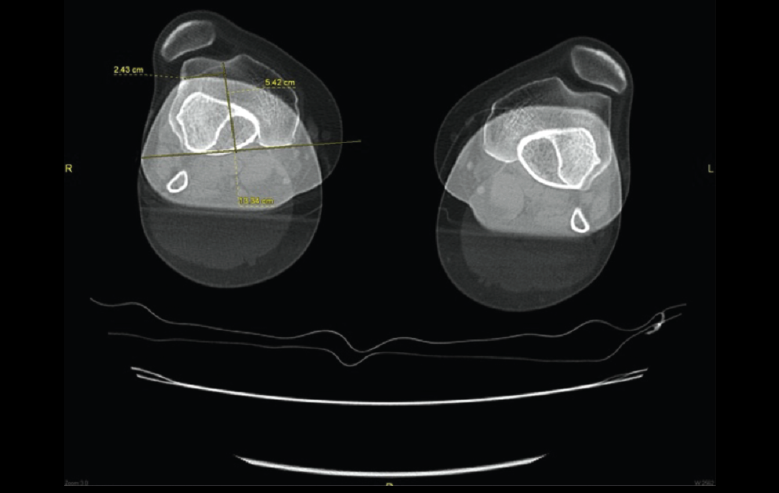

5.1. TA-GT (tuberosidad tibial anterior-garganta de la tróclea)

En pacientes sintomáticos con inestabilidad rotuliana, la TAC es útil para medir la TA-GT(10). La distancia TA-TG es una medida radiológica propuesta por Goutallier y Bernageau que sirve para cuantificar el ángulo Q. Consiste en medir la distancia en milímetros de la tuberosidad tibial anterior a la garganta de la tróclea proyectadas sobre una línea que pasa por los bordes posteriores de ambos cóndilos femorales, superponiendo 2 cortes axiales de TAC. Es una medida fiable y reproducible pero poco precisa, con un margen de error de más de 4 mm. La distancia TA-GT es mayor de 20 mm en el 56% de las inestabilidades rotulianas y tan solo en el 3% de la población sana(11)(Figura 28).

Figura 28. Corte axial de tomografía axial computarizada con superposición de imágenes con rótula y parte posterior de cóndilos y tuberosidad tibial anterior, que nos permite medir la distancia TA-GT, en condiciones normales hasta 2 cm.